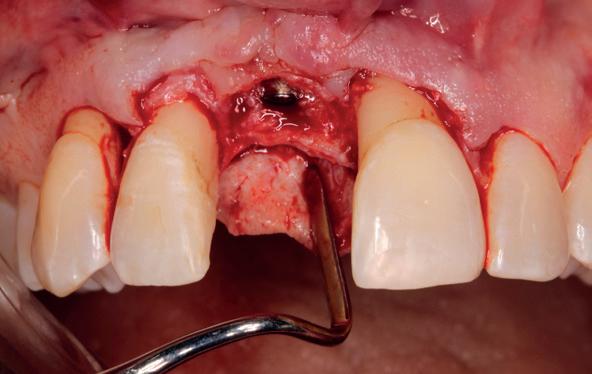

Implantologische behandelingen in het esthetische front vragen meer dan technische vaardigheid alleen. Ze vragen om overzicht, timing, vertrouwen en een team dat als vanzelf samenwerkt onder druk. Juist bij complexe casussen, waarin angst, infectie en hoge esthetische verwachtingen samenkomen, wordt zichtbaar hoe bepalend de rol van de tandartsassistent is.

Deze casus beschrijft een uitgebreide immediate implantaatbehandeling bij een patiënt die door meerdere collega’s werd geweigerd. Niet omdat de mogelijkheden ontbraken, maar omdat de complexiteit vroeg om een perfect afgestemde samenwerking. Het verhaal laat zien hoe de assistent in zo’n traject veel meer is dan een uitvoerende kracht of “mal”, maar een dynamische surgical guide die het proces mede stuurt, bewaakt en mogelijk maakt.De patiënt: wanneer alles samenkomt

Na het klinische onderzoek volgde het röntgenologisch traject. De CBCT liet precies zien wat we al vreesden: een front waarin het bot onregelmatig was, duidelijke radiolucenties rond de pijlers en een infectiegebied dat zich onder vrijwel de gehele brug had verspreid. Tegelijkertijd was er ook potentie. Net voldoende botstructuur om immediate implantaatplaatsing te overwegen, mits alles perfect gepland zou worden.